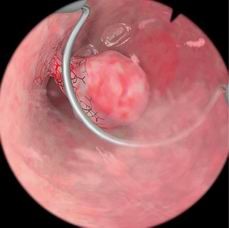

息肉切除模块

病例由易到难,简单的病例可发生在子宫底部,复杂的病例可发生在子宫前壁或者靠近输卵管口的地方